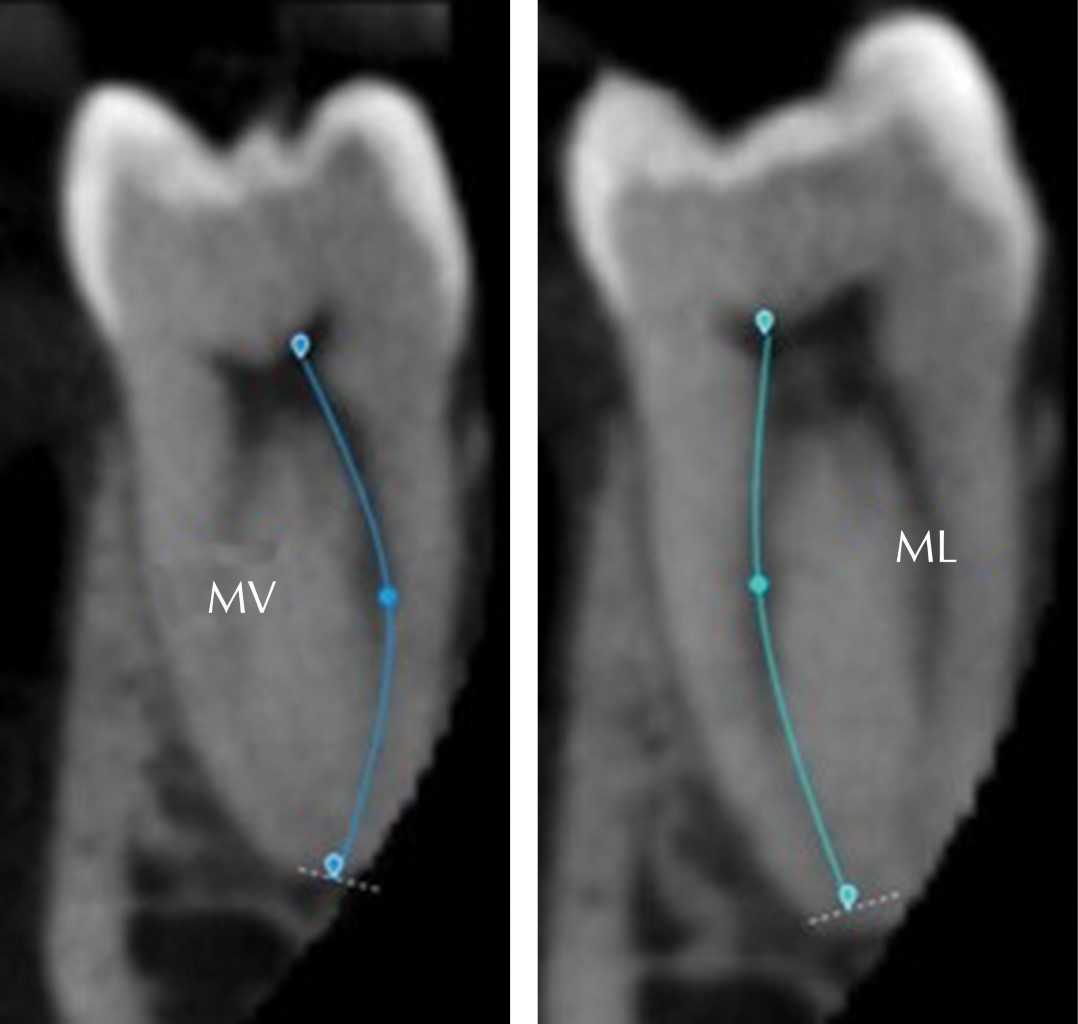

De manera complementaria a las mediciones de las curvaturas de los conductos mesiovestibular (MV) y mesiolingual (ML), en las imágenes de CBCT se pudo detectar que existen muestras que presentan una doble curvatura generalmente en el conducto ML, estas curvaturas se encontraron mayormente en la unión de los tercios medio-coronal y medio-apical respectivamente (Figura 8), en estos casos la mayoría de los conductos MV presentaban una sola curvatura.

Otra forma de observar la posición de las limas en el interior de conductos MV y ML es con la reconstrucción 3D que realiza en forma automática del programa 3D EndoTM (Figura 12).